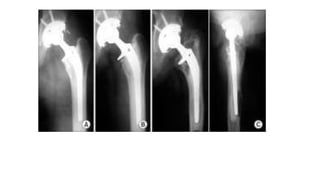

Barrack & Harris Cement Mantle Grading

Grade A: complete filling/ complete white out of cement-bone interface.

upto 10mm distal to prosthesis

no voids / defects/ bubbles

Grade B: Mild Radioluncency at bone-cement interface

Grade C: incomplete mantles/ Radiolucencies > 50% of bone-cement interface.

Grade D: failure of cement to surround the prosthesis/ gross radiolucencies.

Barrack & HarrisCement Mantle Grading Grade A: complete filling/ complete white out of cement-bone interface. upto 10mm distal to prosthesis no voids / defects/ bubbles Grade B: Mild Radioluncency at bone-cement interface Grade C: incomplete mantles/ Radiolucencies > 50% of bone-cement interface. Grade D: failure of cement to surround the prosthesis/ gross radiolucencies.